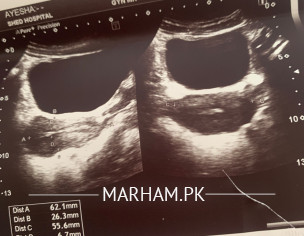

Asking For Self, Female, 22 Years old, north nazimabad

Kindly check my report and reply I’m in tension why is issue? Thankyou